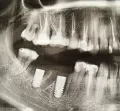

Имплант был установлен 3 месяца назад, когда установили формирователь десны, стало видно, что конструкция находится не посередине десны.

Конечно, Вы верно заметили, имплант стоит не посередине альвеолярного гребня. Возможно, хирург ставил имплант в область максимального объема кости, чтобы избежать дополнительной подсадки кости. Это вынужденная мера и довольно частое явление - хирург вкручивает имплант, куда ему удобно и где больше шансов на приживление, а протезист затем разбирается со смещенным положением.

Могу Вас успокоить вот чем - самое главное, чтобы на рентген-снимке врач увидел хорошее приживление импланта, а судя по Вашей фотографии, коронку изготовить возможно, хотя и немного сложно, но стоять она должна нормально.